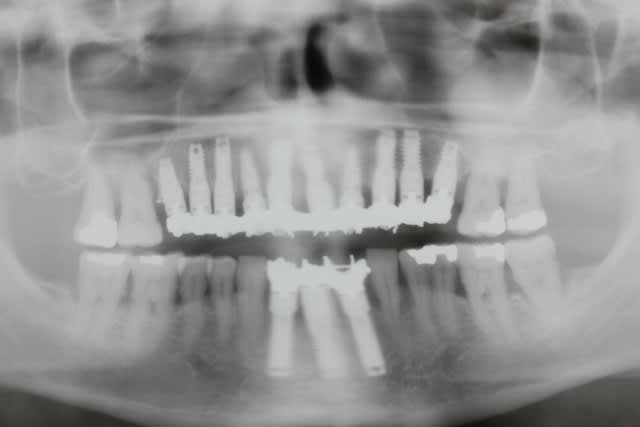

L’imagerie médicale est incontournable et prend toute son importance en implantologie

pour évaluer l’état local et loco-régional. La panoramique permet l’évaluation des foyers

infectieux, dents à extraire, évaluation de la faisabilité implantaire.

Le denta scanner et le cône beam, 3D, permet l’appréciation du déficit osseux. Il confirme

l’atrophie osseuse et précise le capital osseux disponible et l’anatomie des vestibulaires et

palatines.

Des panoramiques de contrôle ont été réalisés, le jour même de l’intervention, 15 jours, 1

mois, 3 mois, et un cône beam a été réalisé après 3 mois.